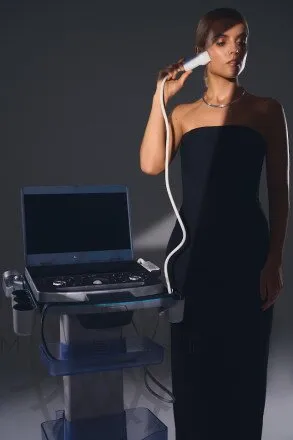

MX7 в косметологии

Применение ультразвуковых технологий в эстетической медицине:

Ультразвуковые датчики в эстетической медицине:

- Визуализация постановки филлеров

- Контроль инъекционных методик

- Визуализация SMAS-слоя

- Оценка расположения сосудисто-нервных пучков

- Контроль при постановке нитевых имплантов

- Оценка васкуляризации кожи и рубцовой ткани

- Определение толщины дермы

- Оценка гидратации дермы и содержания коллагеновых структур

- Диагностика злокачественных новообразований кожи

Ультразвуковые датчики в эстетической медицине:

- L20-5S - линейный высокочастотный датчик

- L13-3NS - линейный датчик